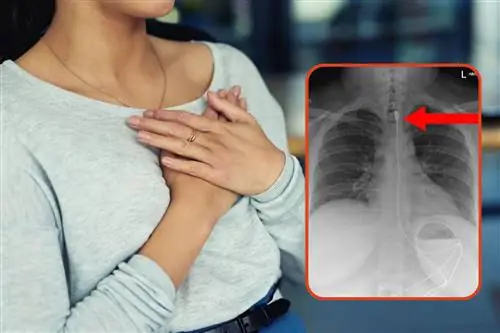

- С чем сталкиваются спасательные команды, а затем и спасательные службы больниц? Со многими темами, которые для обывателя кажутся просто невероятными, невозможными, "а как так получилось?", "как же так?" - спрашивают «Готов к спасению». К сообщению они прикрепили многозначительное рентгеновское фото, на котором виден силовой кабель для зарядного устройства.

Женщина проглотила метровый кабель питания смартфона. Она сообщила спасателям о ситуации только тогда, когда начала ощущать одышку, вызванную наличием инородного тела в верхнем отделе пищевода.